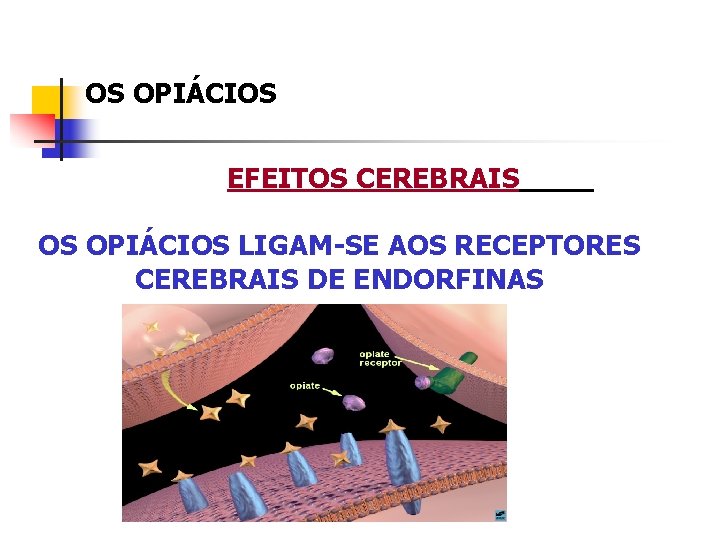

OS OPIÁCIOS EFEITOS CEREBRAIS OS OPIÁCIOS LIGAM-SE AOS RECEPTORES CEREBRAIS DE ENDORFINAS